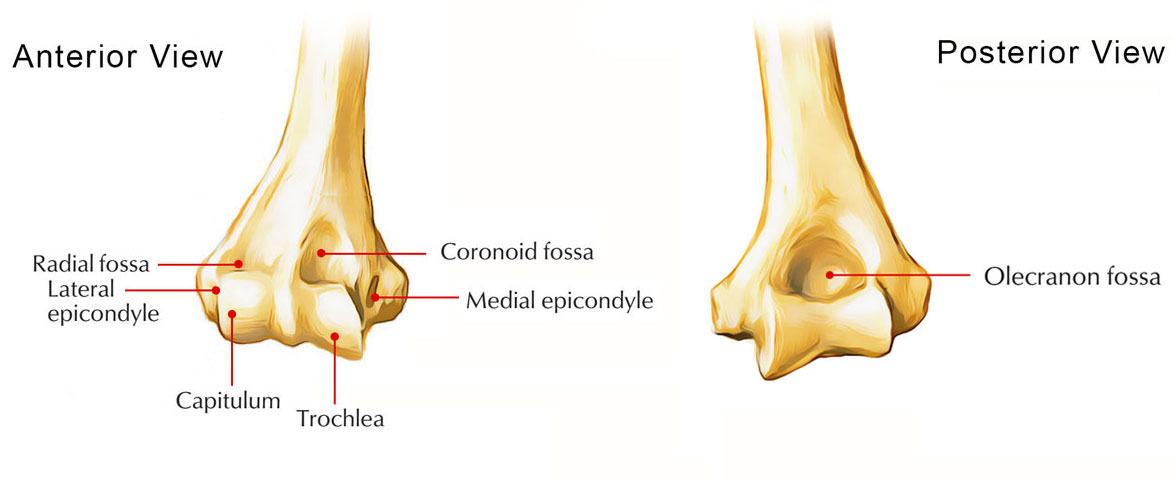

The anterior fat pad is often visible on the normal elbow as a small, radiolucent focus tucked close to the anterior humeral cortex with its visible outline approximately following the line of the adjacent bone. It usually nestles within the coronoid fossa, the anterior depression in which the coronoid process of the ulna parks on full flexion of the elbow. When pushed up and out by an effusion, this fat pad is raised into a characteristically triangular shape to form the sail sign.

The posterior fad pad sits inside a bony recess, the olecranon fossa, which is there to allow full extension of the elbow by housing the olecranon process. When pushed out by an effusion, the posterior fat pad sits proud of the olecranon fossa and becomes appreciable on a well-positioned lateral.